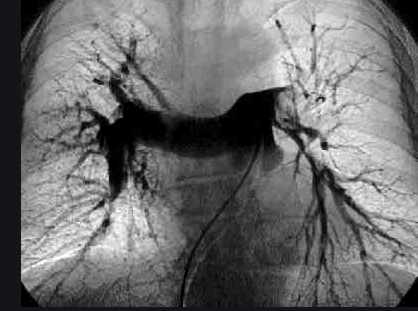

Diagnóstico y tratamiento eficaz para tu tromboembolia pulmonar

Si has tenido síntomas o has sido diagnosticado con tromboembolia pulmonar, no esperes para buscar atención especializada. Como cardiólogo intervencionista en CDMX, puedo ofrecerte el diagnóstico y tratamiento más avanzado para proteger tu salud.